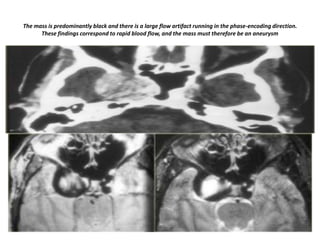

The mass is predominantly black and there is a large flow artifact running in the phase-encoding direction.

These findings correspond to rapid blood flow, and the mass must therefore be an aneurysm